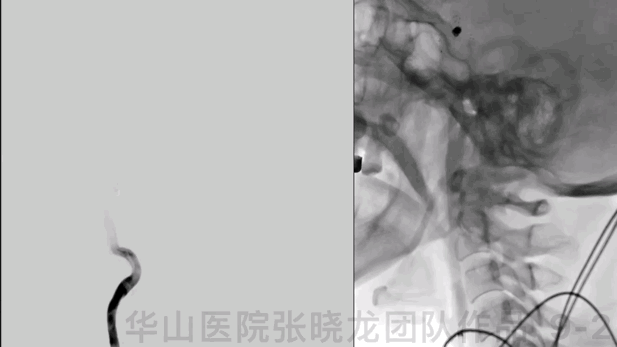

Figure 6. Measurements: size 2.46*3.33mm, neck 2.21mm, proximal parent artery diameter 3.4mm, distal parent artery diameter 3.3mm. 6F Envoy DA guiding catheter was placed into the right cavernous segment. SL-21 microcatheter was advanced into the right posterior communicating artery. Then changed to another working projection. XT-27 was placed into the right M1 segment and deployed Neuroform 3.5*15mm stent.

图 6. 测量:动脉瘤大小2.46*3.33mm ,瘤颈2.21mm,近端载瘤动脉直径3.4mm,远端载瘤动脉直径3.3mm。6F Envoy DA导引导管置于右侧海绵窦段,SL-21微导管在微导丝导引下置于右侧后交通动脉。更换工作角度,将XT-27微导管超选至右侧M1段,于颈内动脉末端内释放Neuroform 3.5*15mm。